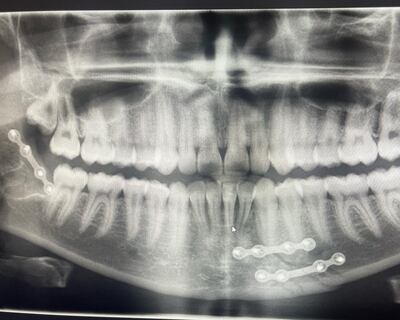

Later in hospital the 21-year-old was diagnosed with two fractures to the jaw. The Kildare man was in severe pain and could feel his jaw bone and teeth “swimming around” in his mouth following the attack.

“Where my jaw was fractured, my teeth had more or less sunken down and there were big gaps that hadn’t been there before. I couldn’t move my mouth and the swelling had started,” he says.

Since the attack last weekend he has undergone surgery to have pins inserted into his jaw bone. They will be a permanent addition. He faces six to eight weeks of a liquid diet until his jaw recovers. He laughs about the fact he may lose a bit of weight.